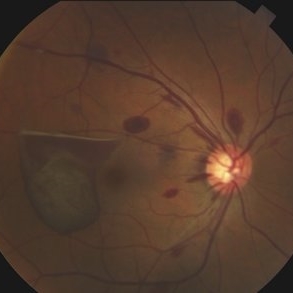

Retinal Hemangioblastoma

May 15 2013 by Robert T. Wendel, MD

20-year-old male. Genetic hx not yet defined.

Condition/keywords: Von Hippel-Lindau